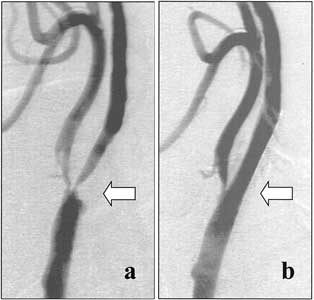

Die Halsschlagader leitet das Blut vom Herzen zum Kopf. Wenn sie zu sehr verkalkt ist, besteht die Gefahr, dass das Gehirn nicht mehr richtig mit Sauerstoff versorgt wird: Es drohen dann Schlaganfälle. Als Gegenmaßnahme wird darum über die Leistenarterie ein Ballonkatheter in die hirnversorgende Hauptarterie eingeführt. Die Engstellen können dann aufgedehnt werden, zusätzlich lässt sich eine Gefäßstütze einbauen, ein so genannter Stent. Der soll dafür sorgen, dass die Schlagader auf Dauer durchlässig bleibt.

Doch mit diesen Komplikationen ist heute nicht mehr zu rechnen, wie Schanzenbächer sagt. Seit 2001 stehen nämlich spezielle Filtersysteme zur Verfügung, die noch vor der Manipulation mit dem Katheter an der Engstelle vorbeigeführt und unterhalb der Schädelbasis zur Entfaltung gebracht werden. Ihre Aufgabe ist es, die Bestandteile der Gefäßwand, die sich bei der Behandlung möglicherweise ablösen, aufzufangen. Auf diese Weise können neurologische Symptome verhindert werden.

Wenn das Gefäß schließlich gut genug aufgeweitet ist, wird der Filter entfernt. Die Punktionsstelle an der Leiste wird mit einem speziellen System verschlossen, so dass die Patienten unter Umständen unmittelbar nach dem Eingriff wieder aufstehen können. Sie müssen dann noch drei Monate lang eine blutverflüssigende Kombinationstherapie einnehmen, um die Bildung eines Blutgerinnsels am Stent zu verhindern.